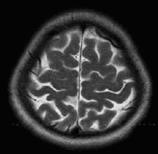

The above algorithms can be used to analyze CT and MR medical images [2] in order to discover modified parts of human tissues. The WFDM shows the areas which require a further investigation. We present below some MR images of human brain and the associated WFDMs.

In the following example the algorithms reveal a very small modified area in a MR brain image.

In the next example we apply a binary filter on the WFDM of a MR brain image to reveal the asymmetry of the tissue.